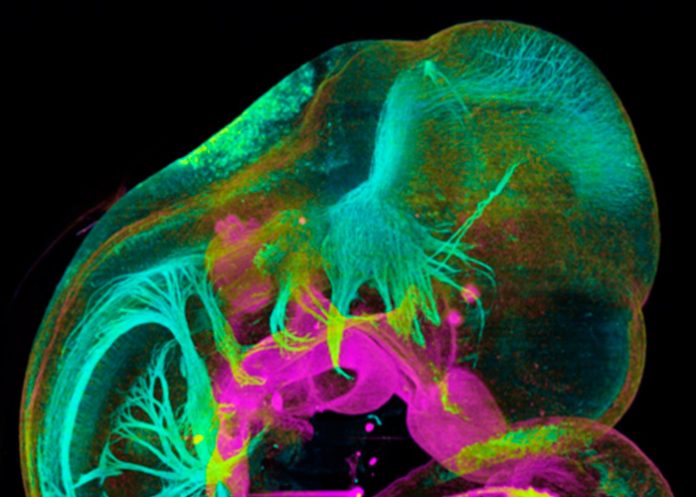

Entre estas tecnologías, destacan especialmente imágenes en 3D y 4D, transcriptómica multicelular y modelaje computacional.